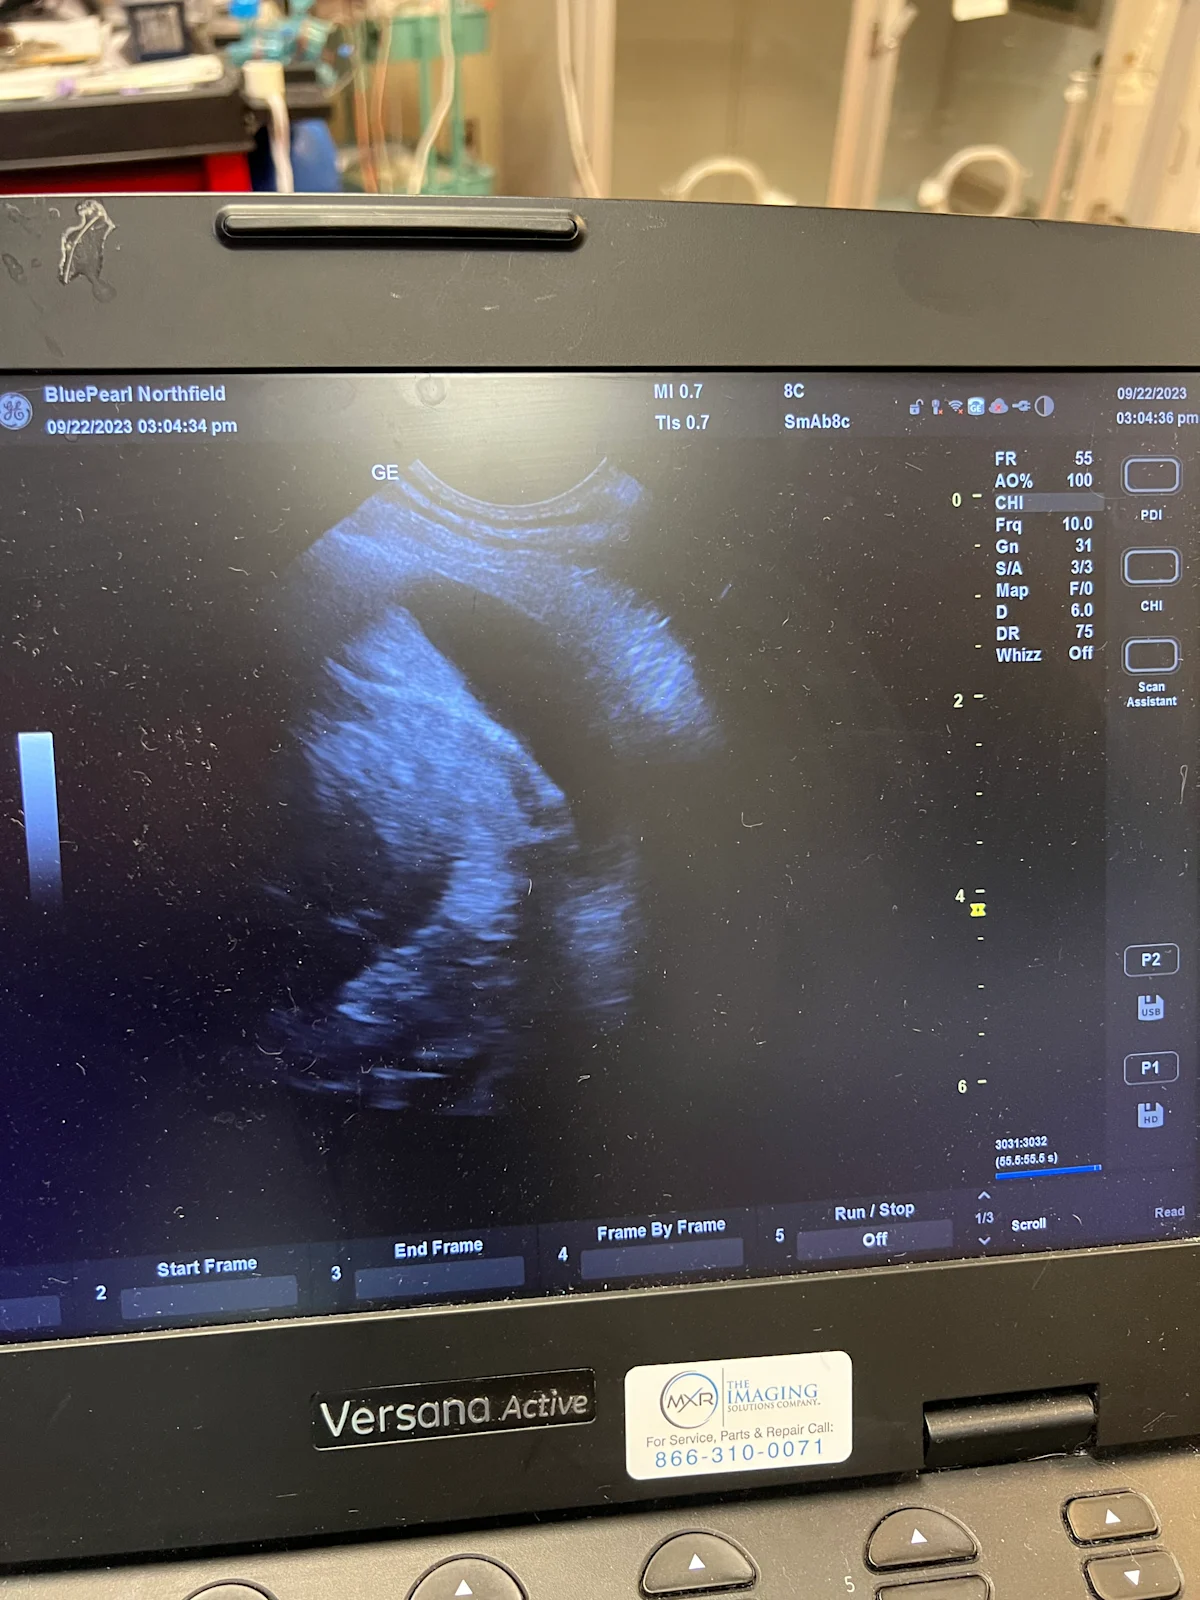

The diagnostic test of choice for identification of pleural effusion is point-of-care ultrasound (POCUS) using thoracic focused assessment techniques that minimize patient restraint and stress.3,4,6,11,13-15 Thoracic radiography can be used if focused ultrasound is unavailable; however, care should be taken to minimize stress in patients with respiratory distress by administering a mild, short-acting sedative (eg, butorphanol, 0.2-0.4 mg/kg IV, SC, or IM16), using fear-free restraint techniques, and/or obtaining a single-view radiograph (lateral or dorsoventral) to allow quick diagnosis. Three-view thoracic radiographs should be obtained following thoracocentesis and patient stabilization.

Use POCUS (if available) to direct the anatomic location of the tap.

On ultrasound, pleural effusion appears as an anechoic pocket separating the lung lobes from the thoracic wall.

Step 7: Post-Tap Assessment